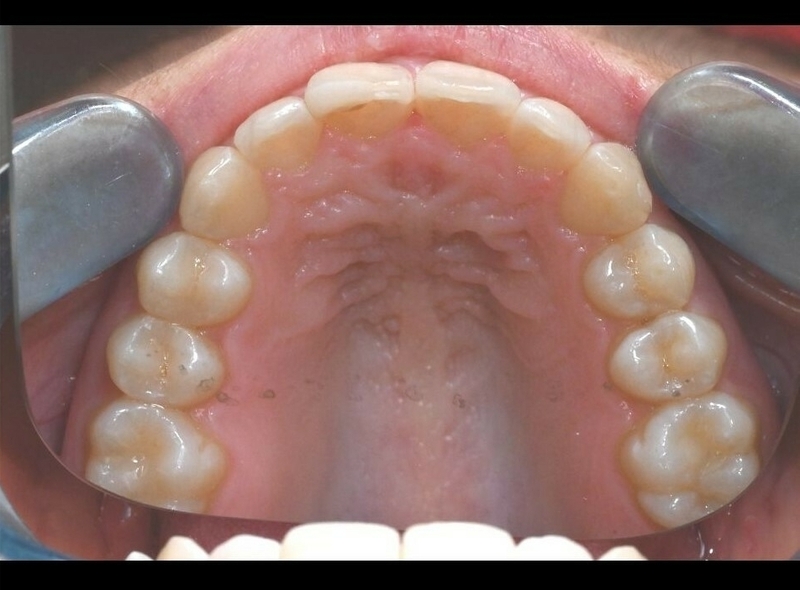

Cas 1 - Parodontie

Après